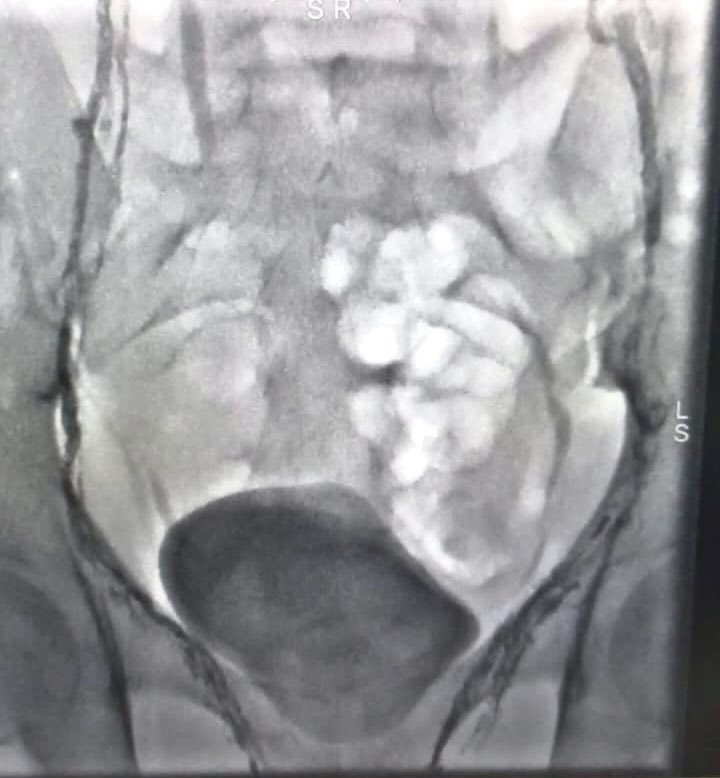

مريضة من ذوي الاحتياجات الخاصة تعيش في قرية صغيرة خارج الرياض تعاني من البدانةالمفرطة . تعرضت لتجلطات حادة في الاورده السفليه للبطن والحوض وتم التعامل مع الحاله بنجاح من خلال تركيب الدعامات اللازمة مع سحب التجلطات. #الأشعة_التداخلية_خيار_أسهل